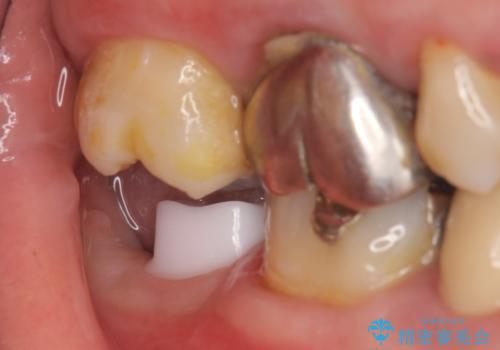

インプラントと骨の定着を待った後に二次手術を行い、カスタムアバットメント、オールセラミッククラウンによる補綴を行いました。

オールセラミッククラウンについて

今回用いたオールセラミッククラウンはジルコニアフレームという白い素材の上にセラミックを盛っているため、審美性が非常に高いのが特徴です。

また、ジルコニアは人工ダイヤモンドの材料にも使われているほど高い強度を持っており、そのためオールセラミッククラウンは審美性だけでなく、奥歯やブリッジの補綴も可能とするクラウンです。